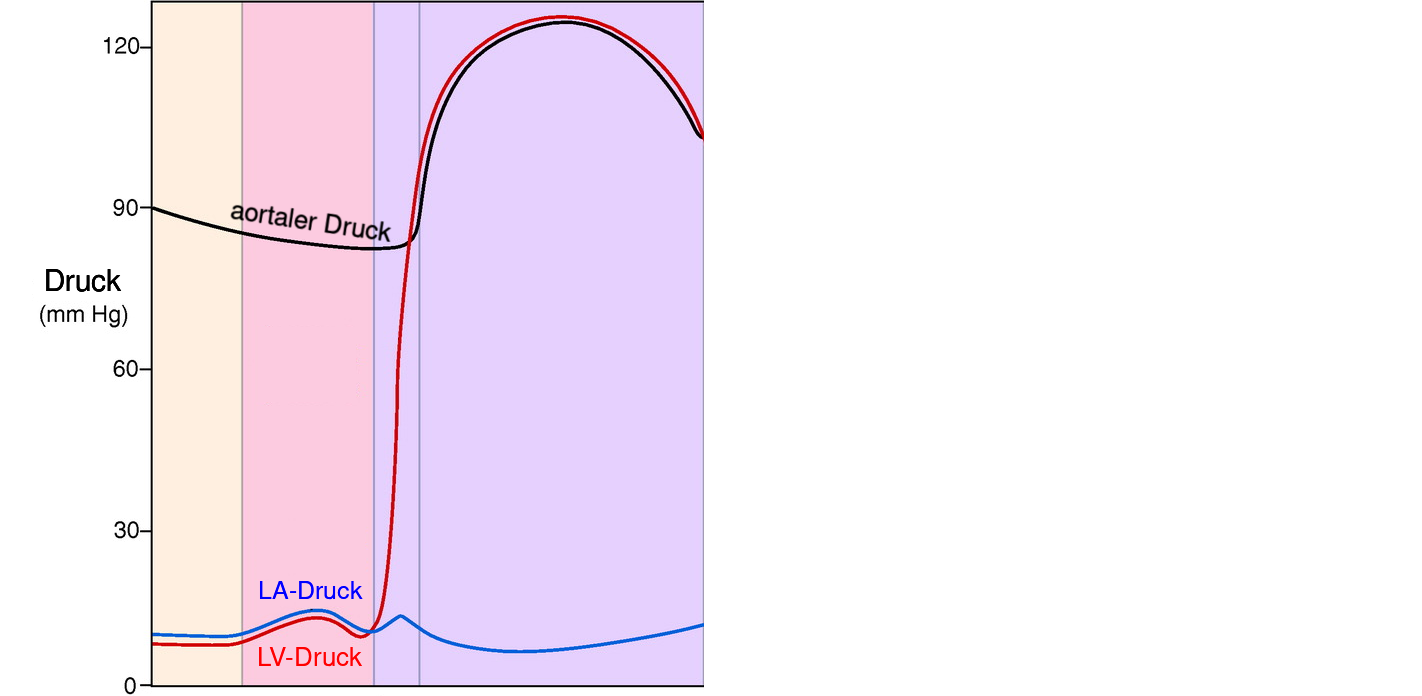

die ventrikuläre Systole (kardialer Output)

- durch die Kontraktion hervorgerufene Inwärtsbewegung der Herzmuskelwand steigt der Druck in der Herzkammer —

- wenn der Druck in den Herzkammern den Druck in der Aorta übersteigt, wird Blut ausgeworfen —

1. Phase Diastole: isovolumetrische Relaxation

- Zeitraum zwischen Aortenklappenschluss und der Mitralklappenöffnung

- Druck im linken Herzen nimmt bei gleichbleibendem Volumen ab

- rascher Druckabfall

- Aufdrehen (Untwist) und elastische Rückfederung (Recoil) des linken Ventrikels ➙ Saugeffekt ➙ Mitralklappenöffnung und Ventrikelfüllung führt

2. Phase Diastole: auxotonische Relaxation

- Zeitraum zwischen Mitralklappenöffnung und atrialer Kontraktion

- mit Mitralklappenöffnung füllt linker Ventrikel mit variablen Druck

- in späterer Phase Entspannung sämtlicher Herzmuskelzellen

- linke Ventrikel nun nachgiebig, leicht dehnbar und weist normalerweise nur minimalem Widerstand gegenüber Füllung auf